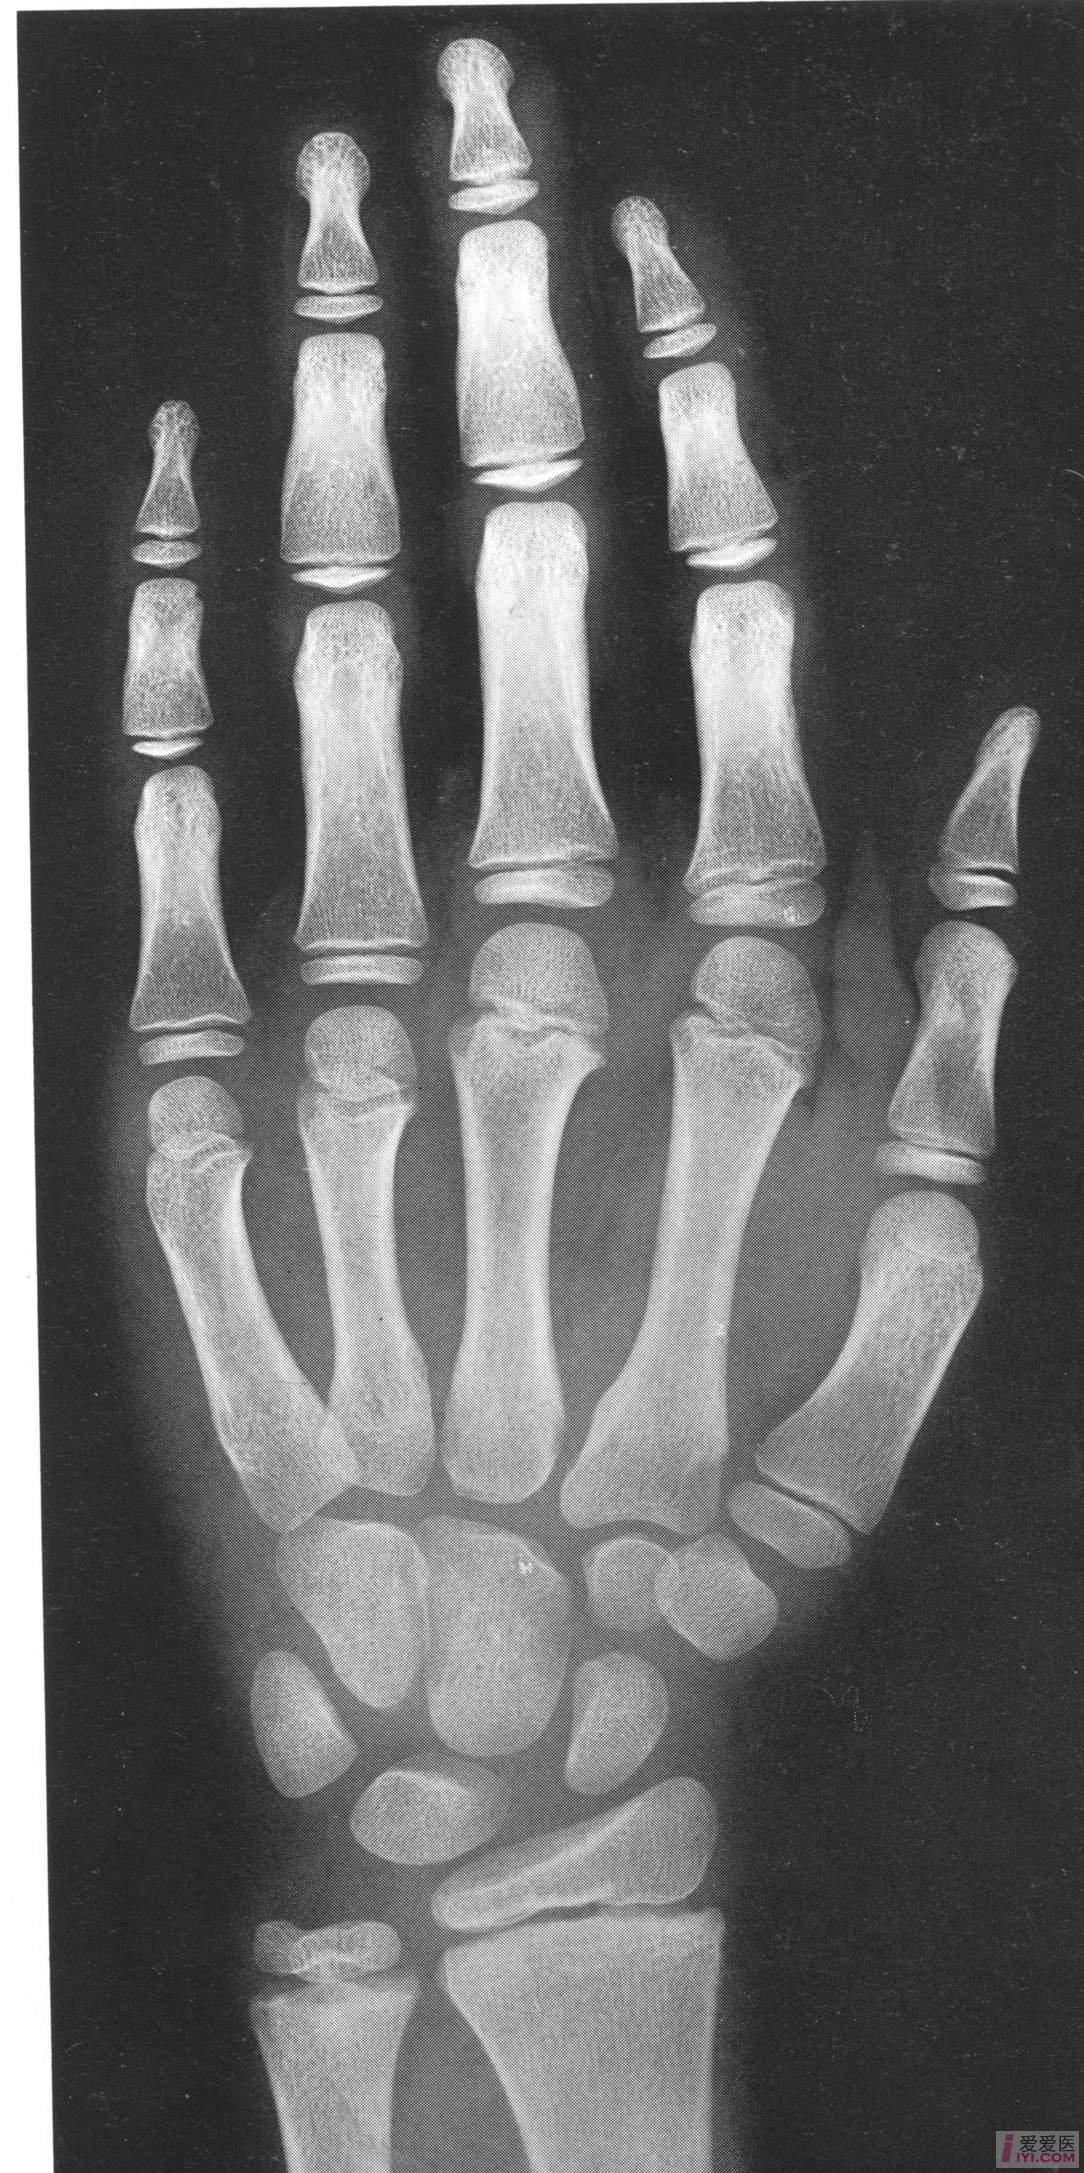

符合女性10岁骨龄

中国儿童标准骨龄片